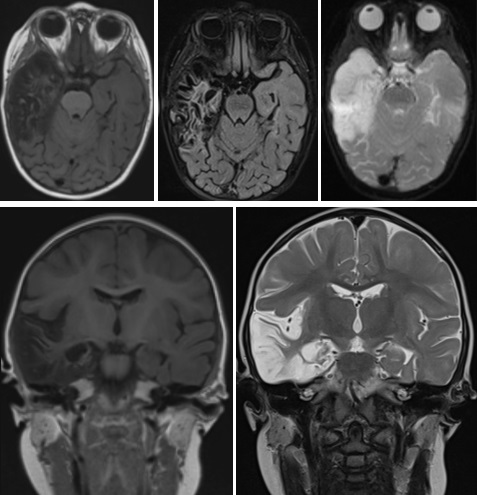

Tras los resultados microbiológicos de la punción lumbar, detectándose en LCR una reacción en cadena de la polimerasa (PCR) positiva para VHS tipo 1, se mantiene tratamiento con aciclovir intravenoso durante 21 días. A los 18 días de ingreso se realiza una resonancia magnética (RM) cerebral en la que se observan secuelas de encefalitis herpética con marcada pérdida de volumen del lóbulo temporal e hipocampo derechos con dilatación compensadora del ventrículo lateral. Así mismo se aprecia sutil pérdida de volumen con prominencia de espacios de LCR a nivel del hipocampo y giro parahipocampal izquierdos (Fig. 2).